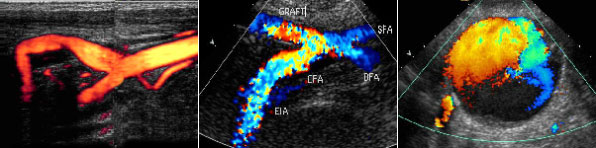

À°¾ÈÀ¸·Î º¸ÀÌÁö ¾ÊÀ» Á¤µµ·Î ±íÀº Á¤¸Æ·ù¿¡ ´ëÇÏ¿©´Â ÃÊÀ½ÆÄÀ¯µµÇÏ¿¡ Ç÷°ü °æÈ¿ä¹ýÀ¸·Î ½Ã¼úÇÕ´Ï´Ù. ÃÊÀ½ÆÄ¸¦ ÀÌ¿ëÇÏ¿© Ç÷°ü°æÈÁ¦¸¦ ÁÖÀÔÇÒ ºÎÀ§¸¦ Á¤È®ÇÏ°Ô Ã£Àº ´ÙÀ½ ÃÊÀ½ÆÄ ȸéÀ» º¸¸é¼ ¾à¹°À» ÁÖÀÔÇÏ´Â ¹æ¹ýÀÔ´Ï´Ù.